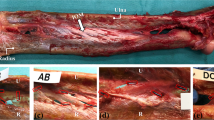

Laser measurements

The humerus and hand were removed from each upper extremity. The forearms were dissected removing all soft tissue down to the radius, ulna and IOM. The IOM was viewed under a dissecting microscope at a magnification of 40X and any additional soft tissue was removed. The length of the radius was measured using a digital caliper, and thickness measurements were made along the length of the radius. The specimens were clamped in a supinated position and a SK-031 laser system connected to a RD controller (Keyence Corp, Saddlebrook, NJ, USA) was positioned on both sides on the IOM (Fig. 2). The thickness measurement range of the laser system was set at an upper limit of five millimeters with a resolution of one micron and a spot diameter of thirty microns. The system linearity was ±0.1% of full scale with a sampling time of 512 μs (technical specification for SK-031 CCD laser displacement sensor; Keyence Corp). Axial IOM thickness measurements were obtained at 3.2-mm intervals at radial, central and ulnar locations along the entire length of the radius. The distance between measurements was limited by the laser-attachment slot spacing. The thickness of the IOM was grouped by location and plotted against the position along the radius. The main and dorsal oblique bundles were identified for each specimen.

A Laser system setup. The laser was positioned perpendicular to the interosseous membrane and advanced in 3.2 mm increments using the slots in the apparatus. B IOM measurements were obtained at ulnar, central, and radial locations. The white area in the central location illustrates the laser-beam measurement location